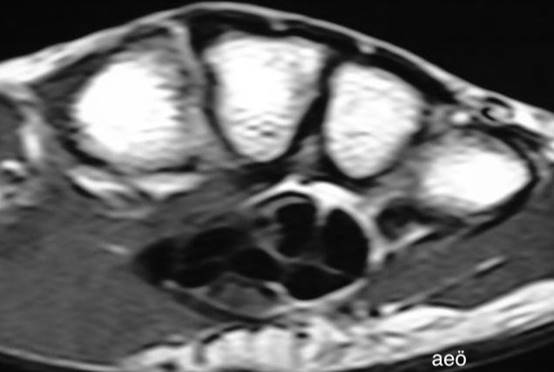

Şekil

2a. El bileğinin kesit

anatomisi (U: ulnar sinir, UA: ulnar arter, FR: fleksor

retinakulum, M: median sinir, H: hamatum,

C: capitatum, Tpzo: trapezoideum, Tpzi: trapezium).

2c. Akut karpal tünel sendromu saptanan hastanın el bileği MR

görüntüleri. Median sinir ödemli ve kalınlaşmış olarak izleniyor (ok).